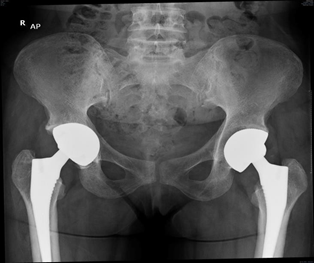

There are many skeletal abnormalities that affect hip joint and femur in sickle cell disease patients, including abnormal shape of femur metaphysis with thin cortex, decreased bone density, and medullary hyperplasia. Irregular sclerotic areas in the bone obliterate canal of the femur and finally loss of congruency of the hip joint.7 Thin femoral cortical lining inside the outer cortex sometimes gives appearance like femur within a femur (Figure 1).8

Total hip Replacement (THR) has become the treatment of choice in SCD patients with end-stage hip osteoarthritis resulting from symptomatic AVN. Patients are active young individuals at the time of surgery, that increase the risk of hip implant failure than those individuals having THA for primary osteoarthritis (OA).5 Rates of implant failure have been reported in early studies with arange from 30% to 60% in less than 5 years. This occurs often due to high functional demand of patients leading to failure of implant.9 More recent data showed improvement in survivorship of hip implant, but still overall complications are higher in sicklers relative to those individuals having THA for primary OA.10 Due to the skeletal abnormalities and medical conditions associated with SCD patients having THA, it is very important for the surgeon to understand the expected pre and postoperative course and also intraoperative considerations regarding these patients and how it can differ from patients having THA for primary OA (Figure 2).